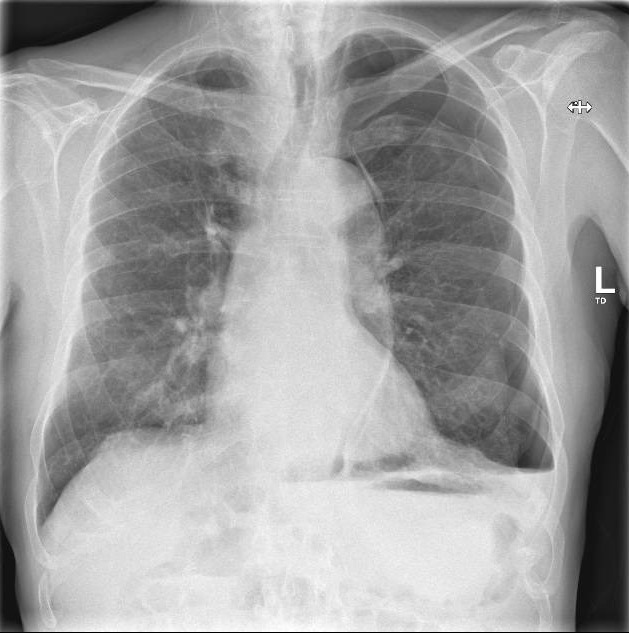

Secondary pneumothoraces can be the first presentation of pleural malignancies and may also complicate their course. They are often associated with prolonged air leaks, and cardiothoracic intervention can be required. https://bit.ly/3DEvPem.

Abstract Image